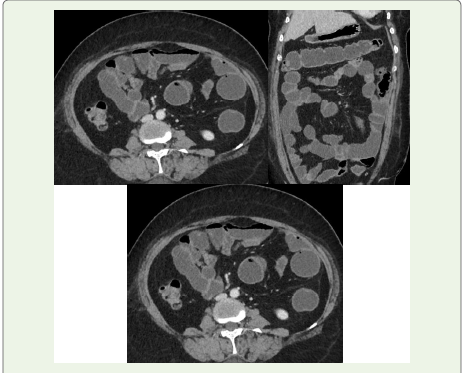

Figure 1:Axial and Coronal CT Enterography: CT combined with luminal

distension of the small bowel by using neutral enteric oral contrast material.